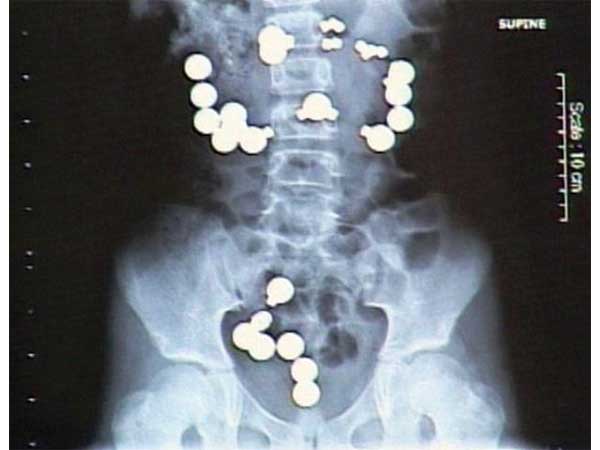

(ছবি) ৯টি অদ্ভুদ জিনিস পাওয়া গিয়েছে মানুষের পেটে!

আসলে আমরা আজ যে বিষয়ে আলোচনা করতে চলেছি সেই বিষয়টাই অদ্ভুৎ। বহু মানুষেরই বিভিন্ন অখাদ্য-কুখাদ্য এমনকী যা খাবার নয় তা খাওয়ার কথাও শোনা যায়। আজ আমরা আপনাদের কাছে এমনই কিছু ঘটনার কথা তুলে ধরব বা বলা ভাল এক্স রে রিপোর্ট দেখাবো, এবং সেই ছবি দেখলে আপনি চমকে উঠবেন।

মানুষের পেটে কীসের কীসের খোঁজ পাওয়া গিয়েছে আসুন দেখে নেওয়া যাক একঝলকে

নেদাল্যান্ডের এক মহিলার পেটে ব্যাথার চিকিৎসা করতে গিয়ে তার পেটে এক্স-রে করে হতবাক ডাক্তাররাই। ওই মহিলার পেট থেকে মোট ৭২টি বিভিন্ন আকার আয়তনে চামচ কাটাচামচ পাওয়া গিয়েছে।

মেথামফেটামাইনের ৫২টি ক্যাপসুল পেটের ভিতর করে নিয়ে গিয়ে পাচার করতে যাচ্ছিল এক নাইজেরিয়ার ব্যক্তি। বিমানবন্দরে ধরা পড়ে সে। এরপর এক্সরে -তে যে ছবি সামনে এল তা ভয়ঙ্কর।